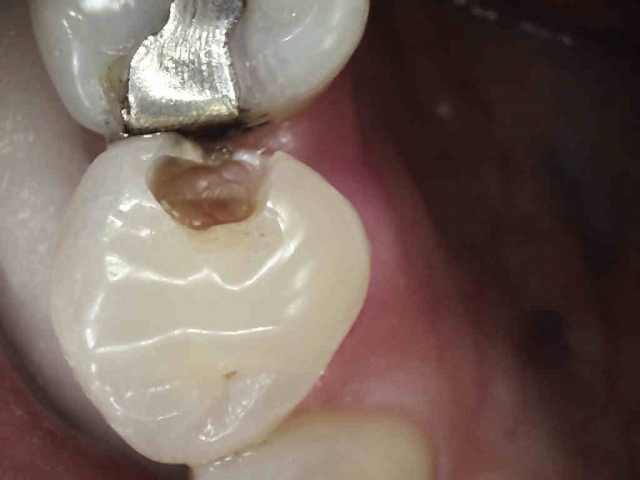

Patient 5: Tooth #18

This patient was referred from a periodontist who was going to extract #19 with socket preservation. The black and white image is deceiving, as they can be sometimes. Here, the mesial does not show a definitive lesion. It is here that the clinical examination is key. Do you examine and chase cracks? If a marginal ridge has a crack that is palpable to your explorer and is discolored, it is leaking. The photo image shows this well. The image that follows shows quite a different story than the black-and-white image. Notice the crack mid-prep is still quite prevalent.